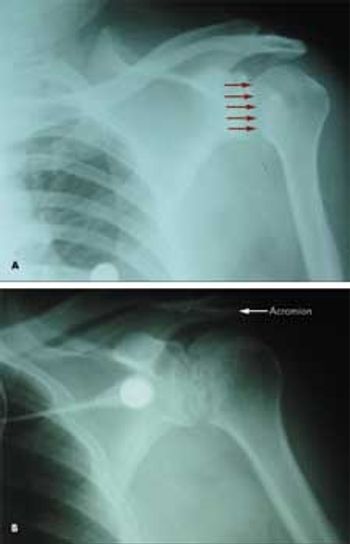

A 53-year-old man with type 2 diabetes mellitus and hypertension presented to the emergency department with pain in his left upper chest and back, neck, and shoulder. The pain increased with passive and active range of motion testing and decreased at rest. His physical examination was unremarkable except for restricted left shoulder movement and generalized tenderness in the left shoulder area.